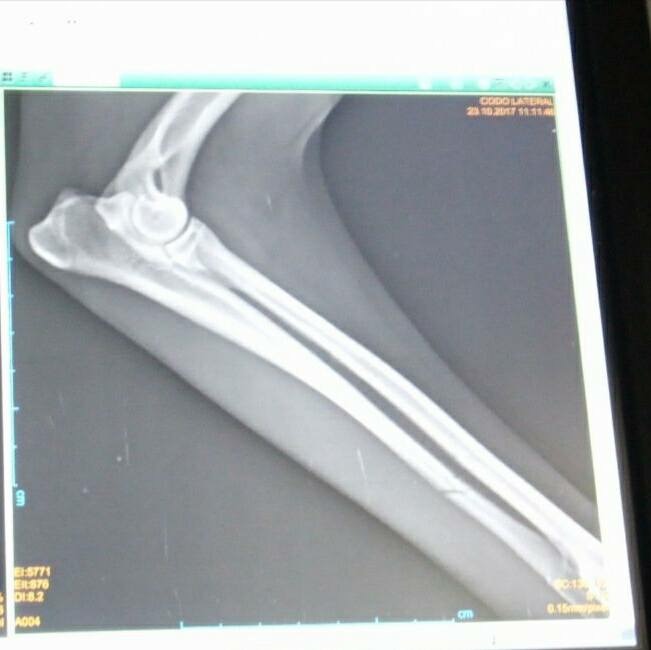

Dieser arme Hund wurde auf einer Straße in Spanien angefahren und einfach liegengelassen. Leider ein alltägliches Bild in Spanien. Zum Glück wurden unsere Tierschützerinnen informiert und haben Osito, wie sie den Rüden genannt haben, gleich in die Tierklinik gefahren. Er wurde geröngt und wird nun in der Klink versorgt. Beide Vorderbeine und einige Rippen sind gebrochen und Osito hat einen Riss im Kopf. Trotz der großen Schmerzen wedelt dieser liebe Hund bei jedem lieben Wort und jeder Streicheleinheit mit seiner Rute. Osito ist ein sehr lieber und geduldiger Patient, der es verdient hat, dass wir ihm helfen. Der Klinkaufenthalt und die nötige Operation kosten ca. 800 €. Unsere Tierschützerinnen benötigen dringend finanzielle Hilfe bei der Deckung der Kosten, die nun anfallen. Vielleicht gibt es ja einige tierliebe Menschen, die sich mit einer, und sei es noch so kleinen, Spende, an der Operation und dem Klinkaufenthalt beteiligen möchten. Jede Spende wird umgehend nach Spanien weitergeleitet. Wir stellen gerne eine Spendenbescehinigung aus. Osito, wir lassen dich nicht im Stich.